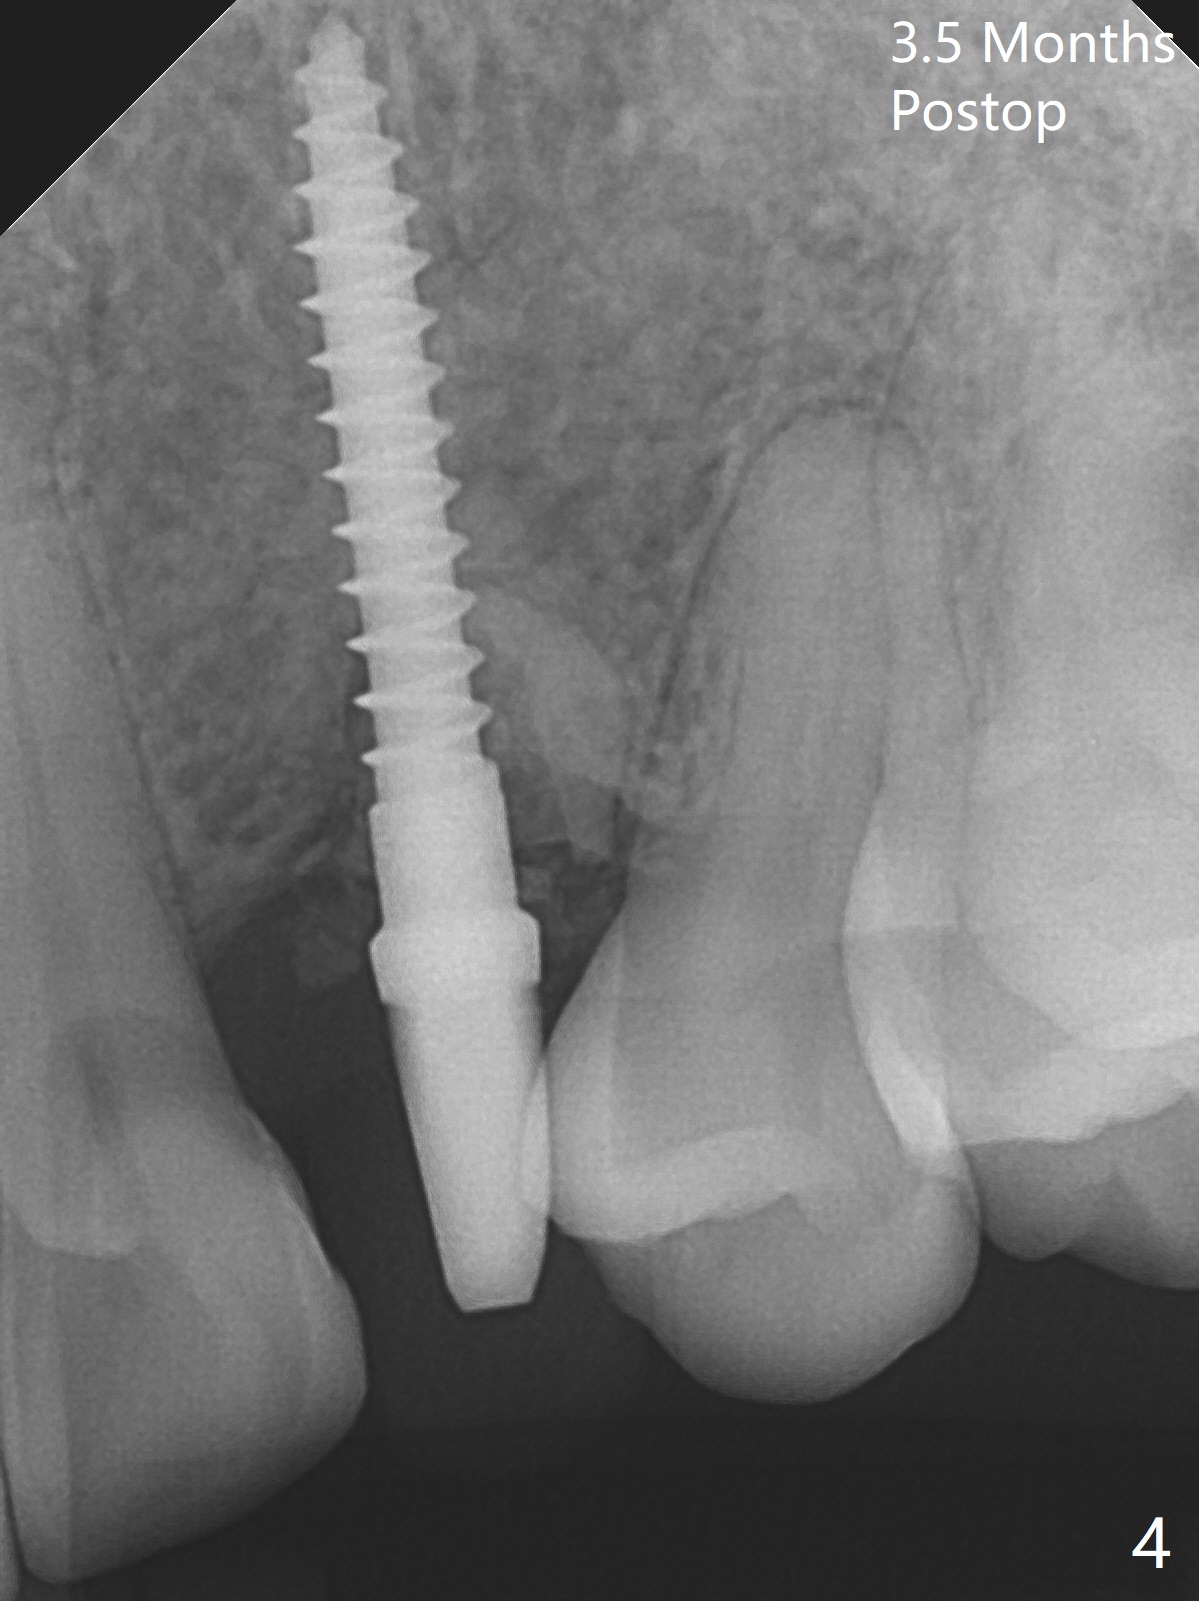

At surgery, the mesiodistal space for #11 is found to be narrow, 5 mm. To prevent buccal plate collapse, socket shield is planned. Due to limited space, incision is attempted so that the lower end of the shield (Fig.1 S) can be trimmed slightly subcrestal. It is also good for visibility for osteotomy (1.2 mm drill for 12 mm). A 2.5x14(2) mm 1-piece implant is placed with <35 Ncm (Fig.2,3 (*: allograft)). An immediate provisional is fabricated to the patient's satisfaction. There is no bone loss 3.5 months postop (Fig.4) or 4 months postop (Fig.5 *, corresponding to S in Fig.3). The recessive papillae are expected to reform to certain degree due to limited damage to the crestal bone.